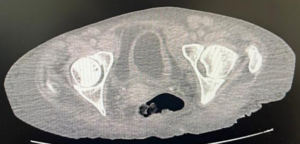

Paciente feminina, 68 anos, negra, que vive com HIV há cerca de 18 anos em tratamento irregular estava internada em unidade hospitalar para investigação de neoplasia linfoproliferativa e durante investigação foi solicitada tomografia computadorizada de abdome e pelve (relato de grande ureterohidronefrose direita e provável compressão ureteral extrínseca ao nível dos vasos ilíacos, com eliminação de contraste do ureter esquerdo em fase tardia), sendo pedido parecer a urologia.